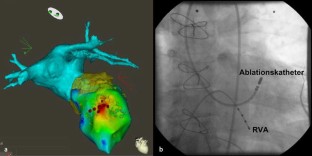

Katheterablation einer linksventrikulären Extrasystolie bei progredienter Herzinsuffizienz

Catheter ablation of premature ventricular complexes in a patient with progressive heart failure

Nach einem stattgehabten Myokardinfarkt kann es aufgrund von strukturellen Umbauprozessen sowohl zu einer hämodynamischen Beeinträchtigung als auch zu einer gesteigerten Arrhythmieneigung des linken Ventrikels kommen. Eine ausgeprägte ventrikuläre Extrasystolie (VES) kann mit ventrikulären Reentryarrhythmien vergesellschaftet sein und selbst zu einer Beeinträchtigung der linksventrikulären (LV-)Funktion beitragen. Ziel des vorliegenden Fallberichtes ist die Darstellung der Ablationstherapie zur Behandlung einer Herzinsuffizienz auf dem Boden einer ischämischen Kardiomyopathie bei einer ausgeprägten, nicht unmittelbar mit der Infarktnarbe in Verbindung stehenden linksventrikulären VES.

Ischemic heart disease is characterized by hemodynamic adaptations and an increased risk of ventricular arrhythmias. Frequent premature ventricular complexes (PVCs) have been associated with ventricular reentry arrhythmias and can promote the worsening of left ventricular function. This case report discusses the beneficial effects of catheter ablation of frequent premature ventricular complexes originating remote from the healed myocardial infarction scar in the treatment of progressive heart failure.